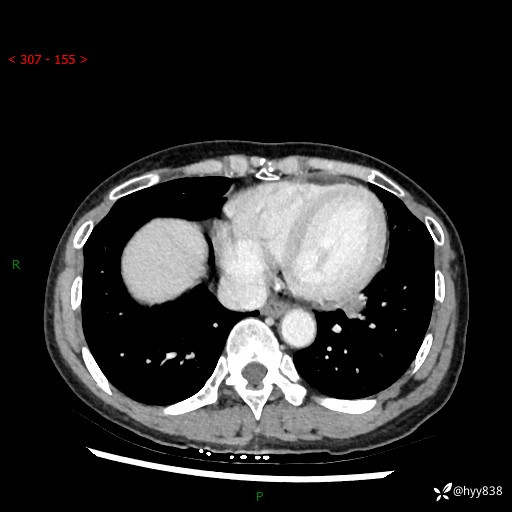

【检查】:胸部CT平扫+增强

各期CT值:40hu 57hu 49hu